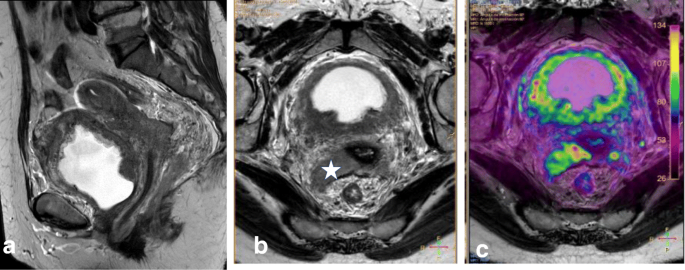

Normal ovaries with follicles or small masses, neural or radicular tumors, and other pelvic masses can be misinterpreted as pelvic metastatic adenopathies. This pitfall can be avoided by careful evaluation of the pelvic structures; identification of peritoneal spaces, extraperitoneal spaces, and lymphatic channels; and analysis of clinical data (Table 6; Fig. 25) [34].

a, b MRI of a 48-year-old woman with known adenomyosis, a previous cesarean section, and FIGO IA1 cervical cancer diagnosed in an outpatient clinic, including sagittal T2WI (a) and axial oblique T2WI (b). No anomalies are visible in the cervix. The cystic image in the right obturator space (arrow in b) was interpreted as a right ovary with a small follicle. The patient underwent simple extrafascial hysterectomy with ovarian removal. Post-surgical histology confirmed FIGO stage IA1 (high-grade squamous cell carcinoma), without LVSI and with a clear surgical margin. c, d MRI was performed 6 months after surgery, including axial oblique T2WI (c) and coronal MIP-DCE sequence imaging (d). The right obturator cystic lesion increased in size and in contact with right iliac vessels (arrows). Images also show medial displacement of the right pelvic peritoneal fascia (red arrowhead) indicating an extraperitoneal origin of the cystic lesion. e 18F-FDG PET-CT shows avid enhancement of the cystic mass. Lymphadenectomy was performed. Histological analysis showed metastatic adenopathy of cervical cancer